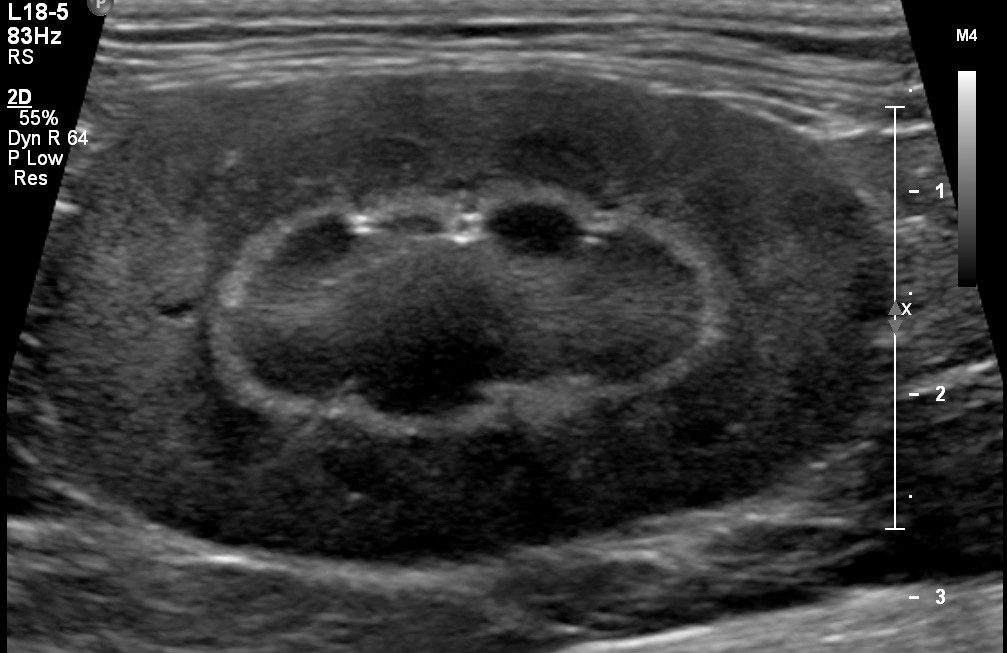

Imaging will include evaluation of the liver, gallbladder and biliary tract, kidneys, adrenal glands, urinary bladder, prostate gland, reproductive tract, gastrointestinal tract, pancreas, intra-abdominal lymph nodes, great vessel, and mesentery. Ultrasound examinations for portosystemic shunts are also available. If warranted, ultrasound-guided aspirates and/or biopsies can be performed subsequent to the initial scan.

Micro-convex, linear and convex probes are used alone or in combination in an effort to visualise all intra-abdominal structures.